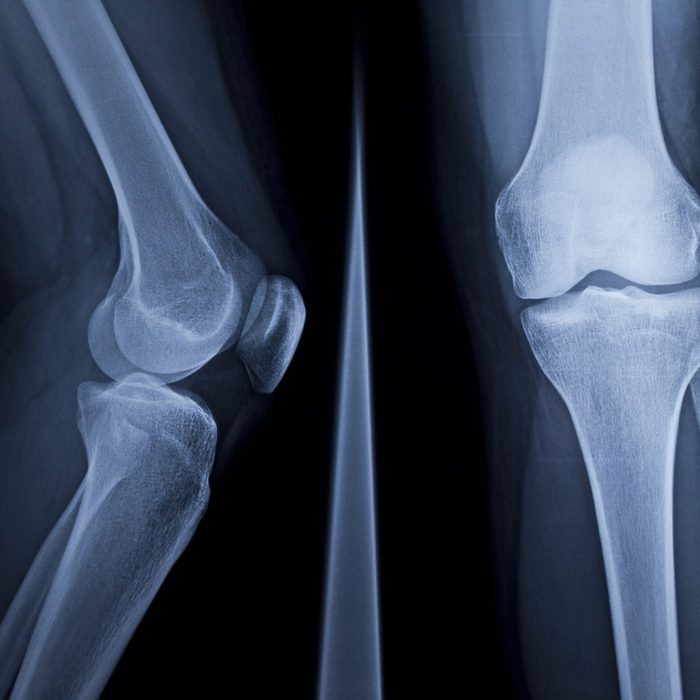

X-Ray of human knee

eyenigelen/Getty Images